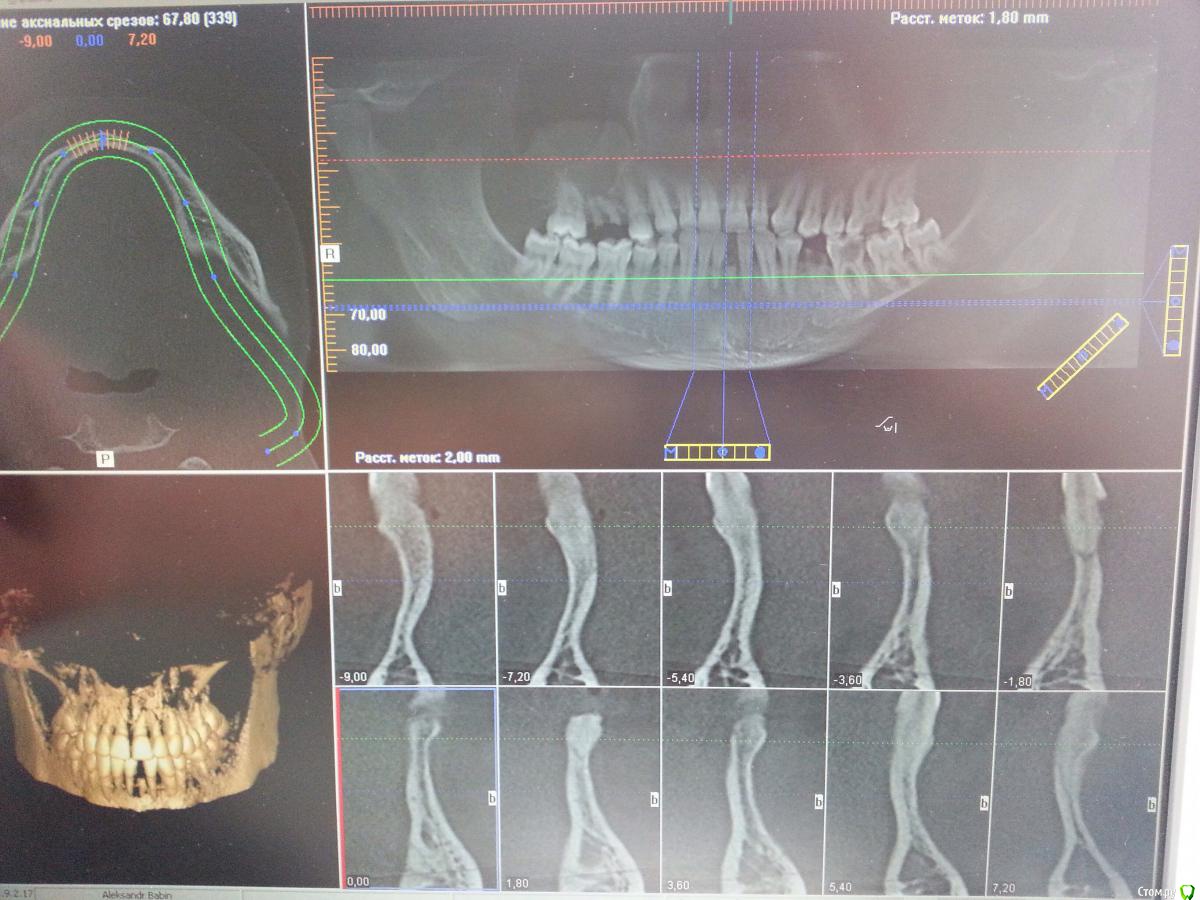

vl. Опубликовано 26 апреля, 2015 Поделиться Опубликовано 26 апреля, 2015 Прошу прощения за качество фото. Планируется: удаление 31,41 Одномоментно 41 (Astra 3.0*13)НКР с пинами вестибулярно и язычно швамиОртопедически планируется консольЧто скажете по поводу моего плана? Какой план предложить Вы? Какие могут возникнуть риски во время операции и после? Ссылка на комментарий

Tabula Rasa Опубликовано 27 апреля, 2015 Поделиться Опубликовано 27 апреля, 2015 Вариант сначала подсадить кость(gbr/блок)->4 мес->имплантация.Форма гребня несуразная.. 1 Ссылка на комментарий